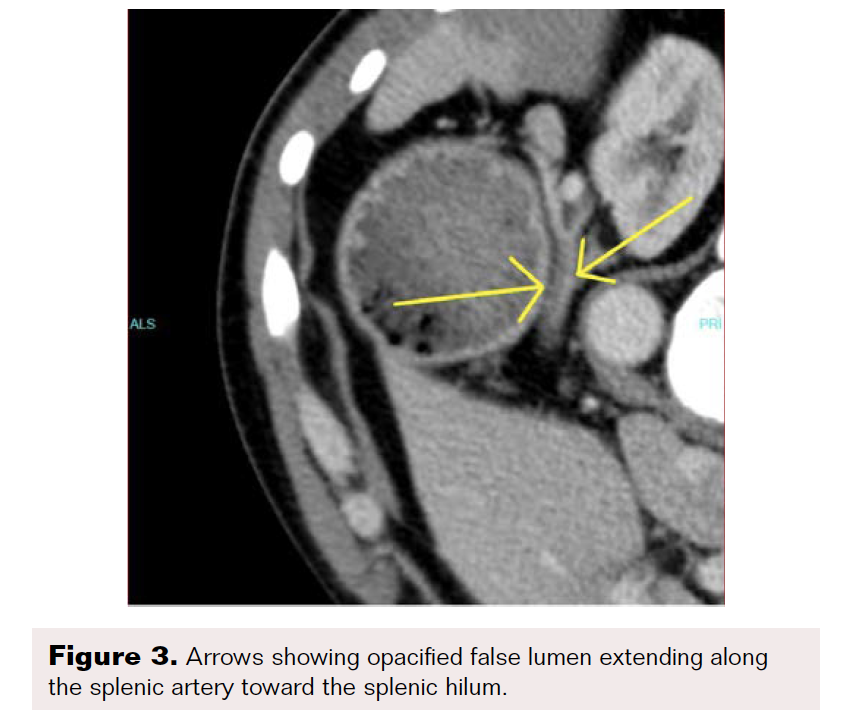

A contrast-enhanced CT scan was completed and revealed stenosis of the celiac trunk and mild bulbous dilatation of the post-stenotic celiac trunk (Figure 1). There was the appearance of a dissection flap that developed into an eccentric hypodense non-enhancing false lumen. This appeared to extend into the common hepatic arterial trunk and the splenic arterial branch, then continued to the splenic hilum (Figure 2 and Figure 3). In addition, there was a large splenic hypo-density involving almost one-third of the central spleen (Figure 4). The findings were consistent with an acute dissection of the splenic and hepatic arteries, along with splenic infarction of the central one-third of the spleen. A differential diagnosis of arcuate ligament syndrome was also considered, given the significant scoliosis seen on scout film of the CT scan (Figure 5).